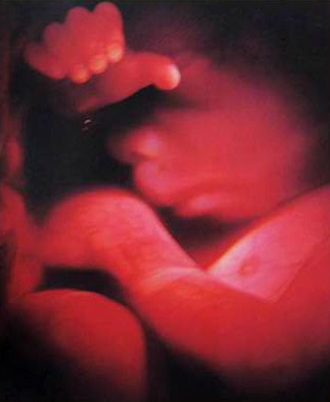

- 필수 검사

- 산전진찰 및 복부 초음파 (1회/2주)

- 막달 산모 종합 검사 (35~36주)

- 태동검사 (34~36주)